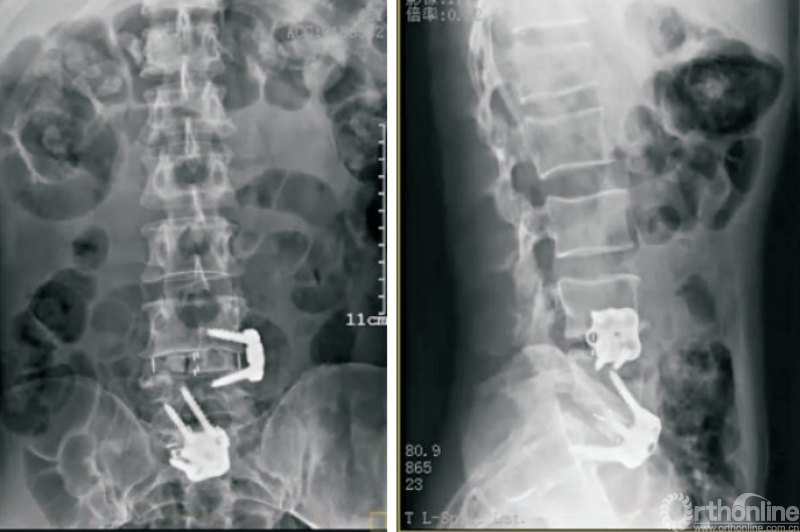

脊柱结核、化脓性脊柱炎等脊柱感染性疾病是脊柱外科的常见疾病,经正规保守治疗无效之后常需要外科手段的介入。经典的前路技术虽然效果确切,但因其手术创伤大、技术难度高等特点而难以在临床广泛展开。通过侧前方入路对脊柱感染部位进行彻底清创,以自体髂骨行植骨融合,联合后路钉棒系统内固定也是有效的治疗腰椎结核的手段(图3)[23-24]

图3 OLIF技术治疗腰椎结核

相较于ALIF组,OLIF技术用于治疗腰椎结核具有出血量少、微创、并发症少等优点。WANG等[25]通过对14例脊柱感染患者经OLIF技术清创、取髂骨植骨融合的疗效分析证实,对于金黄色葡萄球菌、布鲁氏菌、肠杆菌等引起的腰椎感染,OLIF技术均是有效且安全的治疗手段。TONG等[26]经过长期随访也证实,OLIF技术联合后路钉棒系统内固定是治疗抗生素无效的单节段自发性化脓性腰椎间盘炎的有效方案。因此,对于抗生素治疗无效的腰椎感染性疾病,OLIF技术是一种微创、有效的解决方案。